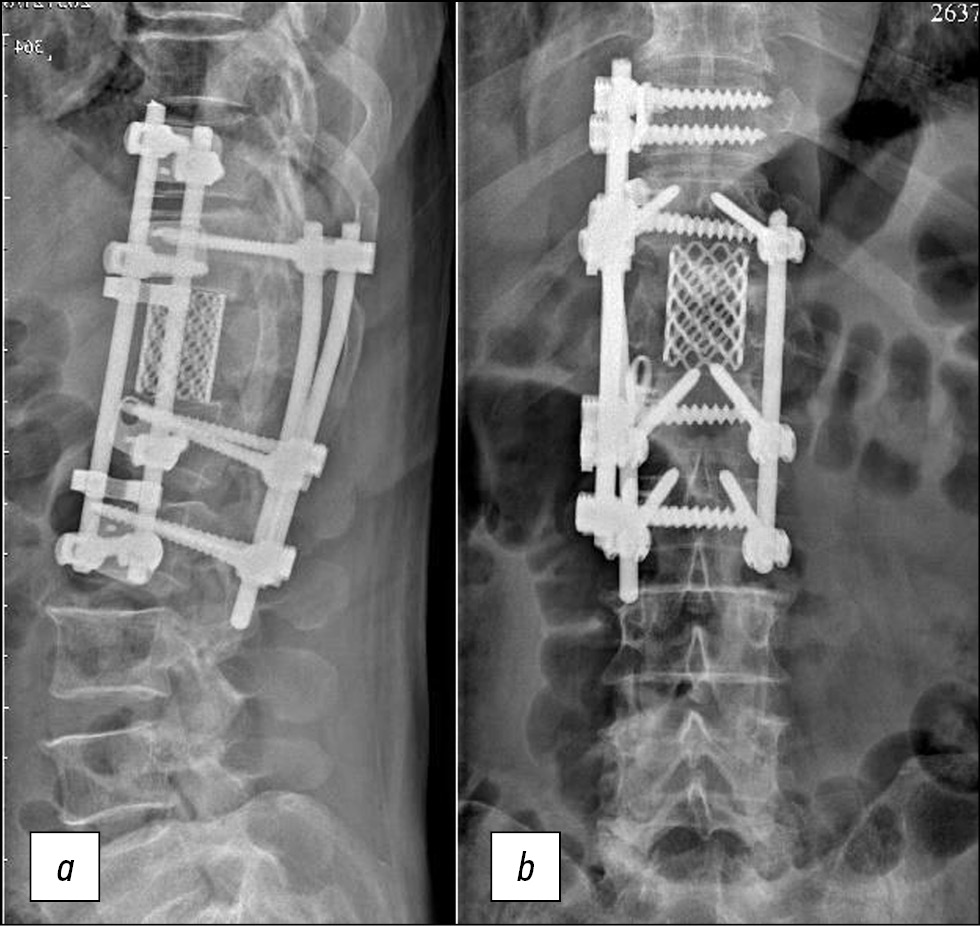

После операции отрицательной динамики в неврологическом статусе не выявлено. Плевральный дренаж удален на 4-е сутки. Со 2-х суток начата поэтапная активизация больного в вертикальном положении, а на 5-й день пациент уверенно ходил без дополнительной опоры. Контрольные рентгенография и КТ, выполненные на 10-е сутки, показали правильное расположение элементов металлоконструкции (рис. 3 и 4).

Рис. 3. Рентгенограммы позвоночника больного Е., 71 год, после операции, прямая (a) и боковая (b) проекции.

Рис. 4. Компьютерная томограмма позвоночника больного Е., 71 год, после операции, боковая (a) и прямая (b) проекции.